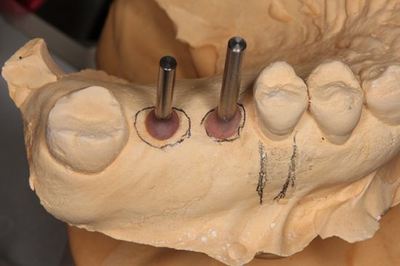

左上臼歯部にインプラント治療を計画します。

2本のインプラントの埋入を予定します。

角度の決定を終えました。

EZ STENT イージーステントを用います。

スリーブを追加しています。

模型に圧接してステントの完成です。